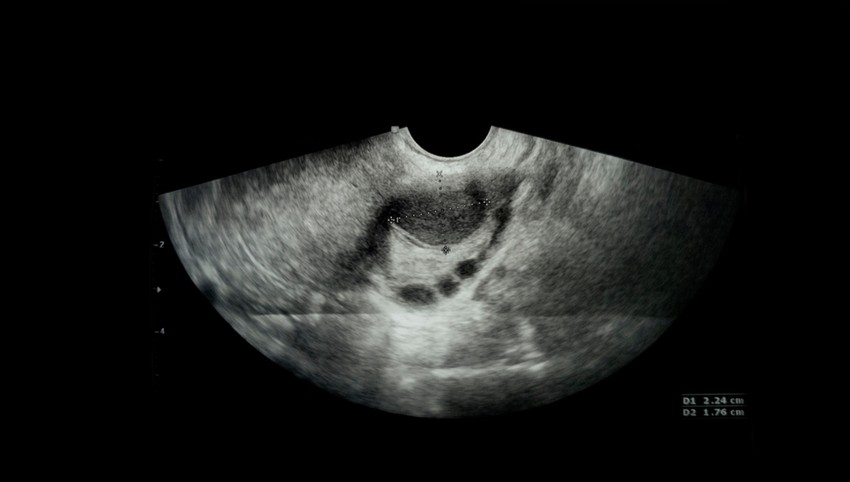

A petefészekciszta kivizsgálása, diagnózisa

A petefészekciszta kismedencei vizsgálat vagy képalkotó vizsgálat, például kismedencei ultrahangvizsgálat során derülhet ki. A petefészekciszta méretétől függően, és attól függően, hogy folyadékkal vagy szilárd anyaggal van-e kitöltve, a nőgyógyásza valószínűleg vizsgálatokat fog javasolni a petefészekciszta típusának meghatározására és annak megállapítására, hogy szükség van-e kezelésre.

A diagnózist felállító orvos számára a legtöbb segítséget az ultrahangos vizsgálat nyújtja. A legfontosabb eldöntendő kérdés, hogy az elváltozás rosszindulatú, vagy sem. A termékeny korban lévő nők esetében a petefészekciszta gyakran jóindulatú, sokkal jellemzőbb a rosszindulatú elváltozás a változókor után.

• Kismedencei ultrahangvizsgálat. Egy pálcaszerű eszköz (transzducer) nagyfrekvenciás hanghullámokat küld és fogad, hogy egy videoképernyőn (ultrahang) képet alkosson az Ön méhéről és petefészkeiről. A kép segítségével megerősítik, hogy cisztája van, megnézik a helyét, és megállapítják, hogy szilárd vagy folyadékkal telt.